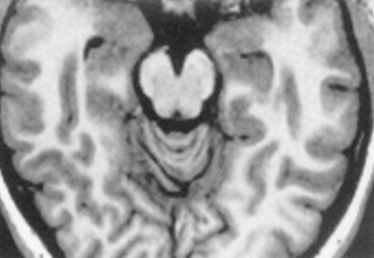

16

Q

which one is T1 and which is T2

A

L: T1

R: T2